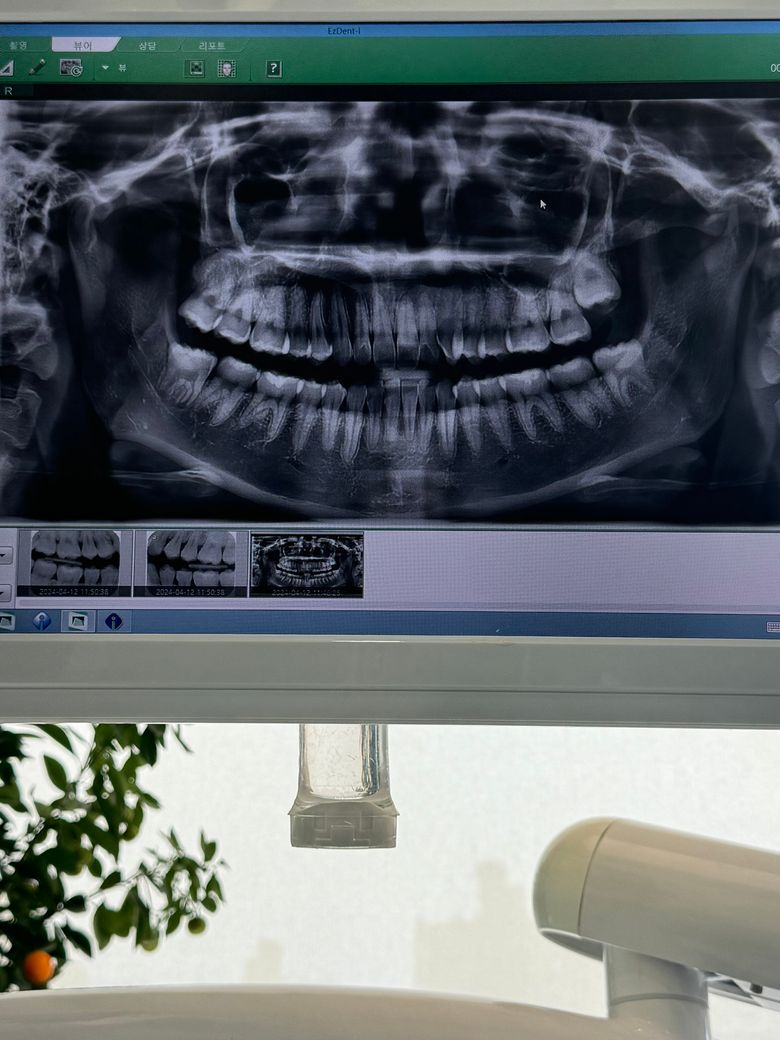

위쪽 사랑니 안났는데.. 바르게 나는거같아보여요..어떻게 생각하시나요? 꼭 발치가 필요할까요?ㅠㅠ 아래쪽만 뽑을건데 ㅠㅠ

사진상에 앞의 어금니와 다소 충돌할 가능성도 있어보입니다. 만약 나오면서 염증 및 통증 붓기가 발생되는 경우에는 우선적으로 발치를 권합니다.

사진으로 봤을 경우에는 사랑니가 똑바로 올라오는 것으로 보입니다. 사랑니가 똑바로 올라와 있고 정상적으로 교합을 하고 있다면 충치가 생기지 않도록 관리를 하면서 사용하는 것이 좋을 수도 있습니다

사랑니는 바르게 자랄 것으로 보이며 사랑니는 특별히 역할이 없고 다른 치아에 문제를 일으킬 가능성이 높은 치아이므로 빼는 게 좋습니다.

왼쪽 위 사랑니를 제외하고는 모두 똑바로 나고 있는 것으로 보입니다. 다만 x-ray 상으로는 판단에 한계가 있으며 정확한 판단을 위해서는 임상검사도 같이 해야 합니다. 똑바로 나고 있는 사랑니라도 관리가 되지 않는다면 발치하는 것이 좋습니다.

안녕하세요 치과의사 김철진입니다. 사랑니가 다 똑바로 맹출될것같습니다. 추후에 맹출이 되더라도 관리가 안되서 염증이 생긴다면 발치를 하시는게 좋습니다.

오른쪽 위 사랑니는 바르게 내려왔고 왼쪽 위 사랑니는 방향은 나쁘지 않습니다 맹출력이 남아있다면 오른쪽처럼 바르게 내려올 가능성이 있습니다